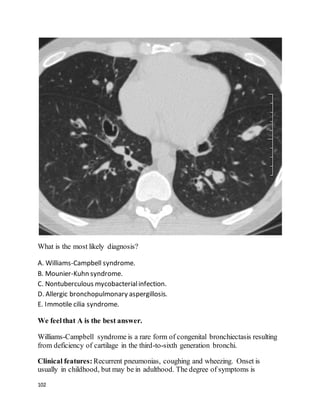

What's the diagnosis?

A. Williams-Campbell syndrome.

B. Allergic bronchopulmonary aspergillosis.

C. Mounier-Kuhn syndrome.

18

D. Cystic fibrosis.

E. Marfan syndrome.

We feelthat C is the best answer.

Mounier-Kuhn syndrome, or congenital tracheobronchomegaly, is a rare inherited

disorder of cartilage formation resulting in enlargement of the C-rings in the

segmental bronchi and trachea. More distal bronchial structures are normal. (This

is in contradistinction to Williams-Campbell syndrome, in which central airways

are normal but distal airways are dilated.) The diagnosis is readily made on a CT

scan showing grossly enlarged central airways, especially with compatible

symptoms.

Clinical presentation is usually with recurrent lower respiratory infections, which

may begin in childhood, or not until young adulthood. Diagnosis was delayed until

age ~75 in a few cases. Productive cough, dyspnea, and poorclearance of

secretions are common symptoms.

Prognosis varies widely and is impossible to accurately predict. Progressive

bronchiectasis (perhaps due to repeated infections), emphysema, and pulmonary

fibrosis are possible. Mild, stable cases, as well as those progressing to respiratory

failure and death, have been reported.